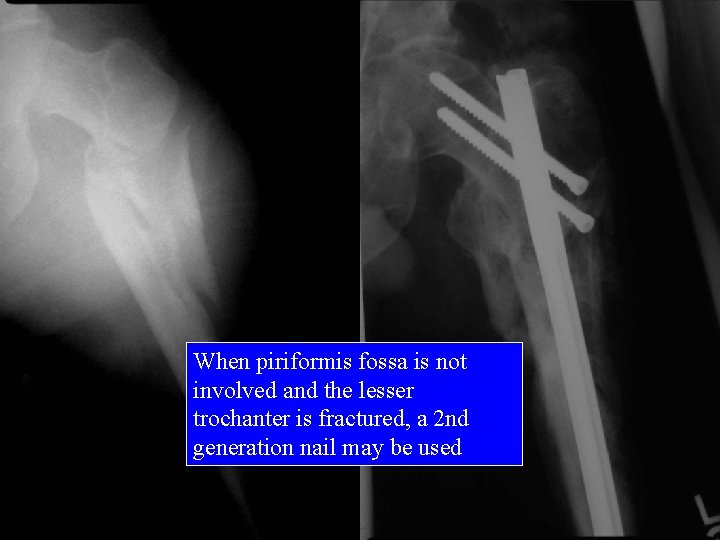

When piriformis fossa is not involved and the lesser trochanter is fractured, a 2 nd generation nail may be used